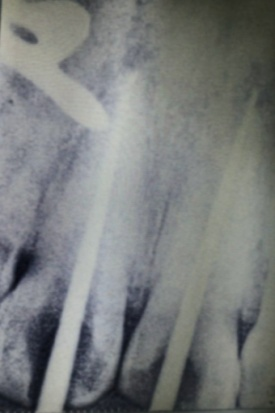

Evaluación radiográfica

La radiografía periapical preoperatoria revela tornillos tipo Dentatus en ambos incisivos centrales sin evidencia de obturación radicular y presencia de procesos periapicales (Fig.3).

Fig. 3 Rx Pre op